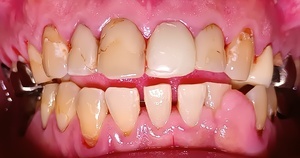

After(歯石除去後)

歯石が除去され、歯の表面が露出しました。歯間も開き、歯間の隙間が見えるようになりました。治療結果には個人差があります。

歯の表面に艶が出て汚れが付きにくくなり、健康的で清潔なお口になりました。